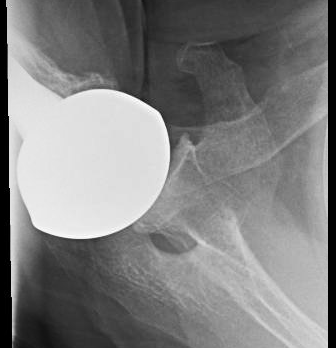

At four years after surgery, he could perform 8 of the 12 SST functions and had the radiographs shown below. Note the impaction grafted humeral stem and the articulation of the prosthesis with the undersurface of the coracoacromial arch.